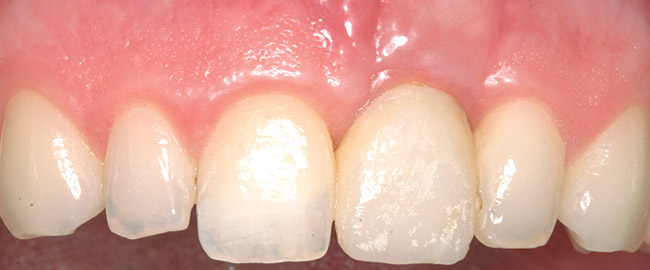

A 59-year-old woman presented with a recent history of trauma to her pre-maxilla, resulting in vertical root fracture of the maxillary left central incisor (Figure 1 and Figure 2). Examination revealed a mobile crown, moderate flat periodontal biotype, gingival margin of the left central incisor 1 mm coronal to that of the adjacent central incisor, central incisor tooth width discrepancy, and a medium smile line. The treatment plan included flapless extraction of the fractured tooth with the potential for simultaneous socket grafting using mineralized bone allograft (MinerOss®, BioHorizons, Inc, Birmingham, AL) and a free gingival graft (Figure 3) harvested from the left palate. Post-extraction examination revealed vertical labial plate loss of 2 mm and class I interproximal height of bone; therefore, all three procedures were performed. Four months postsurgery (Figure 4), a mid-crestal and sulcular incision without release was made to allow for crestal plasty and core biopsy (Figure 5). Histomorphometry revealed 87% vital bone with minimal evidence of residual allograft (Figure 6). This finding was consistent with type II bone density and allowed for non-submerged implant placement. The labial plate was completely regenerated. A provisional crown was placed and contoured to groom the soft tissue for 3 months (Figure 7), followed by final crown fabrication (Figure 8).

Figure 1  Frontal view of the failing maxillary left central incisor.

Figure 1